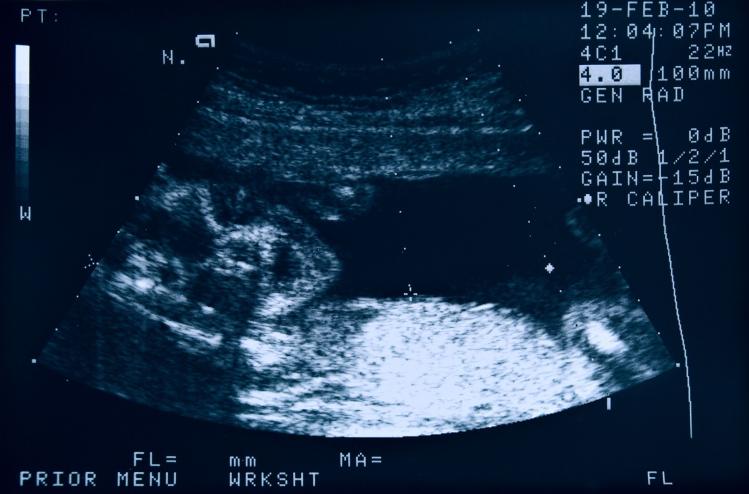

The doctors laughed when I called and told them I was pregnant. A baby conceived with an IUD must really want to be born, they said. I went in to have the IUD removed and to have my first ultrasound. I was the talk of the office. Jokes were made about my husband’s virility. All was well.

But then came the exam, which revealed that the IUD wasn’t there. The doctors said it had likely fallen out. If that was the case, then it wasn’t a surprise that I’d become pregnant. But there was another possibility. There was also a chance, an extremely small one, that the IUD had perforated my uterus. If this was the case, I was told, then the IUD would have to be located and removed, because it could cause serious complications during the pregnancy.

I underwent an internal and external ultrasound and two pelvic exams. The IUD could not be found. The doctors restated their belief that most likely it had fallen out, but it wasn’t something they could confirm. I could carry on with the pregnancy and assume that everything was okay, or I could get an x-ray exam. X-rays pose several dangers to a fetus, including a heightened risk of cancer later on; they can also cause miscarriages. But if the IUD had perforated the uterus and was still somewhere inside me, there could be fatal consequences for the unborn child—including preterm stillbirth.

Already, and completely unexpectedly, I was faced with a decision regarding the life or death of my child. Neither choice seemed better than the other. But I had a nagging feeling that the IUD was still in my body, so I went for the x-ray. And I was right.